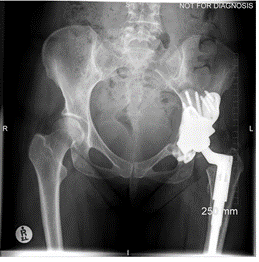

A middle-aged patient came to the clinic with severe pain and limited mobility in his left hip. Previously, he had undergone bilateral hip replacements that included modular necked femoral stems with ceramic-on-ceramic (CoC) bearings. However, the modular design led to corrosion between the titanium femoral stem and the cobalt-chromium neck, causing metal debris and an adverse tissue reaction in his left hip.

The challenge was in addressing the corrosion-related inflammation without exacerbating the damage to the surrounding bone, as the femoral stem was well fixed. Unlike cases with pseudotumors, the patient’s problem originated from metal debris due to the interaction of different alloys in the modular components.

Imaging studies confirmed the presence of metal debris and inflammation around the implant, particularly affecting the left hip. Despite the ceramic-on-ceramic bearing being intact, the corrosion at the modular junction between the neck and the stem was the main culprit. The diagnosis was an adverse reaction to metal debris, secondary to modular neck corrosion.

The surgery was successful, and at his six-week follow-up, the patient reported pain-free mobility and had resumed his daily activities. Imaging showed that the new primary stem had successfully integrated with the bone. At the two-year follow-up, the patient had a well-functioning hip, with no complications and clear evidence of bone growth around the implant, confirming the efficacy of the surgical approach.

This case represents ALTR with CoC. ALTR was characterized by tissue inflammation and extensive fluid accumulation around the ceramic implants. However, ALTR was not caused by the ceramic implant but by corrosion, which occurred between the titanium femoral stem and the cobalt-chromium neck.